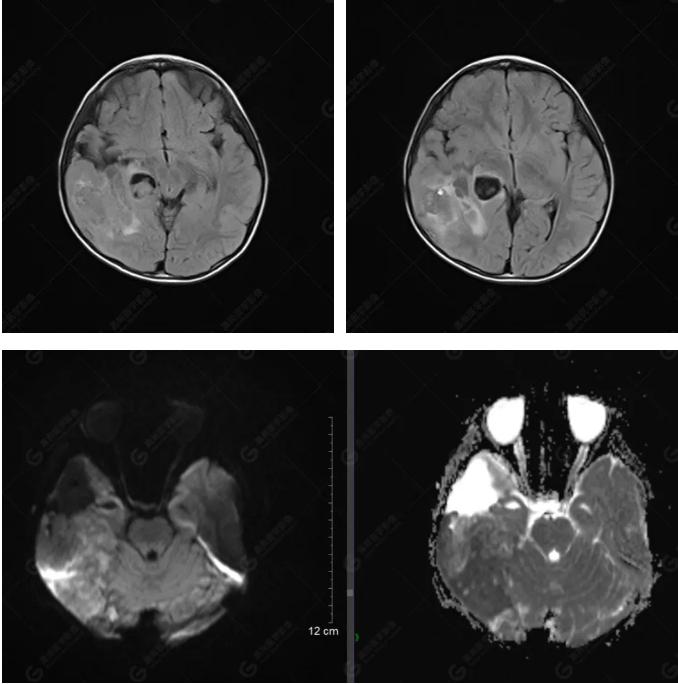

右側(cè)顳葉腫瘤切除術(shù)后(具體不詳):右側(cè)顳部骨質(zhì)不連續(xù)呈術(shù)后改變,右側(cè)顳葉術(shù)區(qū)見(jiàn)片狀長(zhǎng)T1長(zhǎng)T2信號(hào)影,F(xiàn)LAIR呈低信號(hào);術(shù)區(qū)后方右側(cè)顳枕葉見(jiàn)一巨大占位性病變影,邊界欠清,大小約6.2×5.8×4.3cm(前后×左右×上下),信號(hào)不均勻,T1WI呈等稍低信號(hào)間雜少許高信號(hào),T2WI呈高稍低混雜信號(hào),DWI示部分病灶彌散受限,相應(yīng)ADC圖減低,磁敏感序列見(jiàn)部分呈極低信號(hào),增強(qiáng)掃描可見(jiàn)明顯不均勻強(qiáng)化,鄰近硬腦膜及小腦幕增厚并明顯強(qiáng)化;另延髓右前方及右側(cè)橋小腦角區(qū)見(jiàn)一不規(guī)則形異常信號(hào)影,大小約3.2×1.3×3.7cm(左右×前后×上下),呈長(zhǎng)T1稍長(zhǎng)T2信號(hào),F(xiàn)LAIR呈等信號(hào),DWI未見(jiàn)受限,增強(qiáng)后明顯均勻強(qiáng)化,鄰近腦膜明顯強(qiáng)化。鄰近腦實(shí)質(zhì)及右側(cè)顳角明顯受壓;左側(cè)大腦半球未見(jiàn)局灶性信號(hào)異常,中線結(jié)構(gòu)稍左移。

右側(cè)顳葉腫瘤切除術(shù)后:現(xiàn)術(shù)區(qū)后方右側(cè)顳枕葉及延髓右前方占位,右側(cè)顳枕部硬腦膜及小腦幕明顯強(qiáng)化,結(jié)合既往影像資料,考慮為胚胎源性惡性腫瘤,如非典型畸胎樣/橫紋肌樣瘤(AT/RT)或原始神經(jīng)外胚層腫瘤(PNET)。